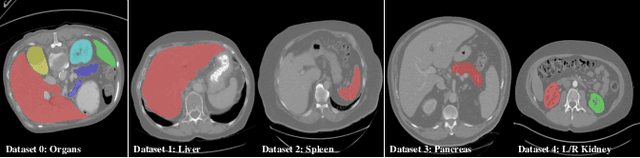

Abstract:Objective and Impact Statement: Accurate organ segmentation is critical for many clinical applications at different clinical sites, which may have their specific application requirements that concern different organs. Introduction: However, learning high-quality, site-specific organ segmentation models is challenging as it often needs on-site curation of a large number of annotated images. Security concerns further complicate the matter. Methods: The paper aims to tackle these challenges via a two-phase aggregation-then-adaptation approach. The first phase of federated aggregation learns a single multi-organ segmentation model by leveraging the strength of 'bigger data', which are formed by (i) aggregating together datasets from multiple sites that with different organ labels to provide partial supervision, and (ii) conducting partially supervised learning without data breach. The second phase of site adaptation is to transfer the federated multi-organ segmentation model to site-specific organ segmentation models, one model per site, in order to further improve the performance of each site's organ segmentation task. Furthermore, improved marginal loss and exclusion loss functions are used to avoid 'knowledge conflict' problem in a partially supervision mechanism. Results and Conclusion: Extensive experiments on five organ segmentation datasets demonstrate the effectiveness of our multi-site approach, significantly outperforming the site-per-se learned models and achieving the performance comparable to the centrally learned models.

Abstract:There exists a large number of datasets for organ segmentation, which are partially annotated and sequentially constructed. A typical dataset is constructed at a certain time by curating medical images and annotating the organs of interest. In other words, new datasets with annotations of new organ categories are built over time. To unleash the potential behind these partially labeled, sequentially-constructed datasets, we propose to incrementally learn a multi-organ segmentation model. In each incremental learning (IL) stage, we lose the access to previous data and annotations, whose knowledge is assumingly captured by the current model, and gain the access to a new dataset with annotations of new organ categories, from which we learn to update the organ segmentation model to include the new organs. While IL is notorious for its `catastrophic forgetting' weakness in the context of natural image analysis, we experimentally discover that such a weakness mostly disappears for CT multi-organ segmentation. To further stabilize the model performance across the IL stages, we introduce a light memory module and some loss functions to restrain the representation of different categories in feature space, aggregating feature representation of the same class and separating feature representation of different classes. Extensive experiments on five open-sourced datasets are conducted to illustrate the effectiveness of our method.

Abstract:In the paper, we present an approach for learning a single model that universally segments 33 anatomical structures, including vertebrae, pelvic bones, and abdominal organs. Our model building has to address the following challenges. Firstly, while it is ideal to learn such a model from a large-scale, fully-annotated dataset, it is practically hard to curate such a dataset. Thus, we resort to learn from a union of multiple datasets, with each dataset containing the images that are partially labeled. Secondly, along the line of partial labelling, we contribute an open-source, large-scale vertebra segmentation dataset for the benefit of spine analysis community, CTSpine1K, boasting over 1,000 3D volumes and over 11K annotated vertebrae. Thirdly, in a 3D medical image segmentation task, due to the limitation of GPU memory, we always train a model using cropped patches as inputs instead a whole 3D volume, which limits the amount of contextual information to be learned. To this, we propose a cross-patch transformer module to fuse more information in adjacent patches, which enlarges the aggregated receptive field for improved segmentation performance. This is especially important for segmenting, say, the elongated spine. Based on 7 partially labeled datasets that collectively contain about 2,800 3D volumes, we successfully learn such a universal model. Finally, we evaluate the universal model on multiple open-source datasets, proving that our model has a good generalization performance and can potentially serve as a solid foundation for downstream tasks.

Abstract:There exists a large number of datasets for organ segmentation, which are partially annotated, and sequentially constructed. A typical dataset is constructed at a certain time by curating medical images and annotating the organs of interest. In other words, new datasets with annotations of new organ categories are built over time. To unleash the potential behind these partially labeled, sequentially-constructed datasets, we propose to learn a multi-organ segmentation model through incremental learning (IL). In each IL stage, we lose access to the previous annotations, whose knowledge is assumingly captured by the current model, and gain the access to a new dataset with annotations of new organ categories, from which we learn to update the organ segmentation model to include the new organs. We give the first attempt to conjecture that the different distribution is the key reason for 'catastrophic forgetting' that commonly exists in IL methods, and verify that IL has the natural adaptability to medical image scenarios. Extensive experiments on five open-sourced datasets are conducted to prove the effectiveness of our method and the conjecture mentioned above.